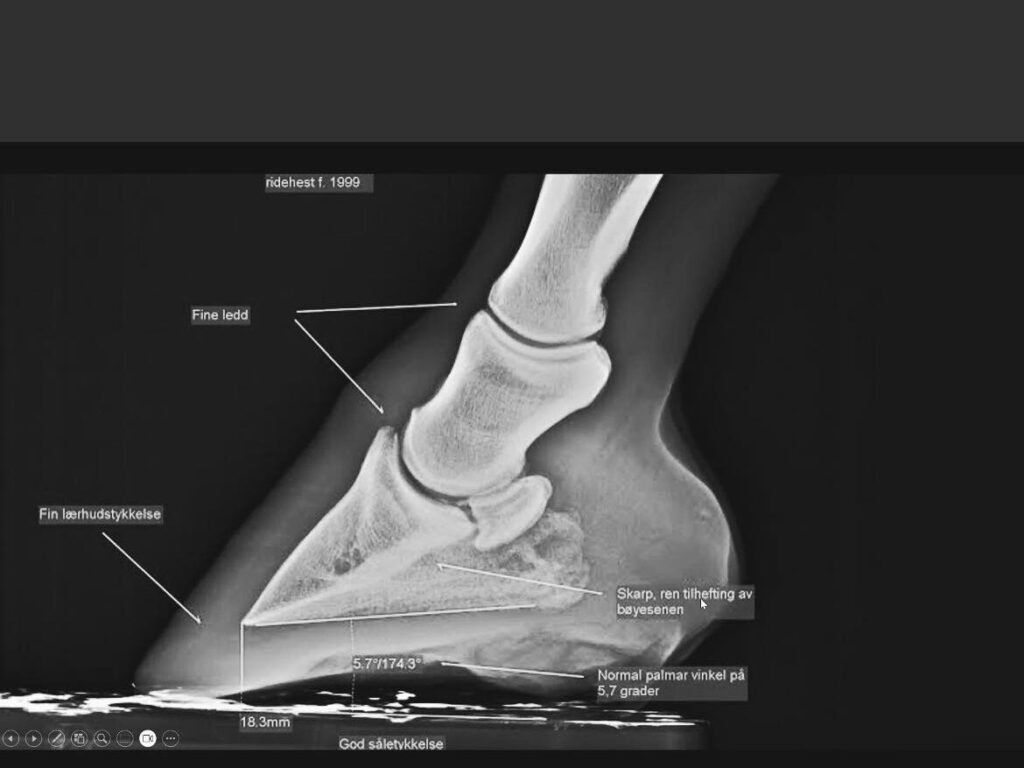

Om att läsa röntgenbilder

26.06.2025 – Digital medlemsträff Att läsa röntgenbilder Väl genomfört medlemsträff, första gången digitalt! Tack till alla som deltog och till veterinär Tone…